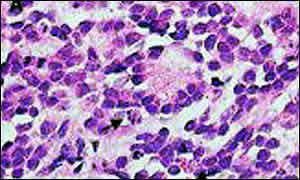

É uma doença maligna que ataca principalmente as crianças. Tumor formado por neuroblastos, (células em estado de divisão celular) que se localizam na glândula supra-renal. O neuroblastoma pode, em alguns casos, apresentar regressão espontânea, mas como é um tipo de câncer muito agressivo, pode aparecer em crianças com idade de até seis meses, sendo assim caberá ao Pediatra detectar a doença e encaminhar.

É uma doença cujas células malignas vão ser encontradas em algum lugar do sistema nervoso periférico, no entanto é mais comum que se estabeleça nas glândulas denominadas adrenais, que se localizam nos rins e são compostas por dois tecidos de origem embrionárias diferentes, um produzindo os esteróides e o outro, os neurotransmissores, são Maravilhas da Engenharia do corpo humano. Existem catalogadas 125 tipos de doenças das glândulas supra-renais, mas a ¨neuroplasia¨ das glândulas supra-renais, é a única que tem o índice 100 de valoração. Essas glândulas são responsáveis pela produção de hormônios e pela defesa dos perigos emocionais, do equilíbrio do sal, entre outros.

Apesar dos estudos científicos sobre a origem da doença, os fatores de risco ainda continuam desconhecidos, já os recursos para um diagnóstico da doença ainda na infância são vários, como por exemplo, a biópsia, que promove a remoção de células do tumor para exames de laboratório, mas ai a doença já existe. Outro método que é muito utilizado e que apresenta bons resultados, é a tomografia computadorizada que fotografa todo o corpo do paciente, auxiliando Como Cuidar Melhor da Nossa Saúde e diagnosticar uma recuperação do paciente. Só para exemplificar, dois atores podem implicar em uma possibilidade mais concreta de recuperação do paciente, a idade e quando diagnosticado, o estado do câncer. Fora isso, é pedir uma Ajudinha de Deus para que à luz da ciência, seja descoberta a sua cura.